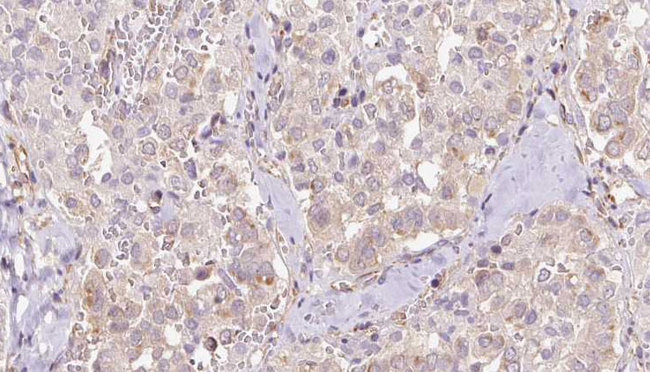

- Main image

- Experimental details

- 1:100 staining human thyroid carcinoma tissue by IHC-P. The sample was formaldehyde fixed and a heat mediated antigen retrieval step in citrate buffer was performed. The sample was then blocked and incubated with the antibody for 1.5 hours at 22°C. An HRP conjugated goat anti-rabbit antibody was used as the secondary.